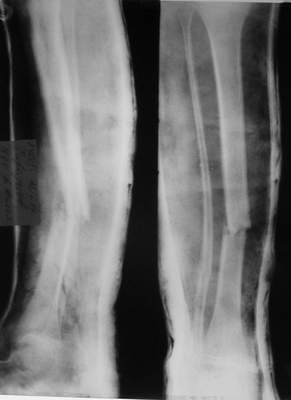

Первичные